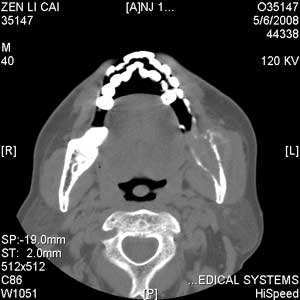

以下是引用jiangjing在2008-5-28 15:56:00的发言:[br]下颌骨左侧部骨质破坏,轻度膨胀,瘤骨形成,软组织肿胀考虑 恶性骨肿瘤-----肉瘤类